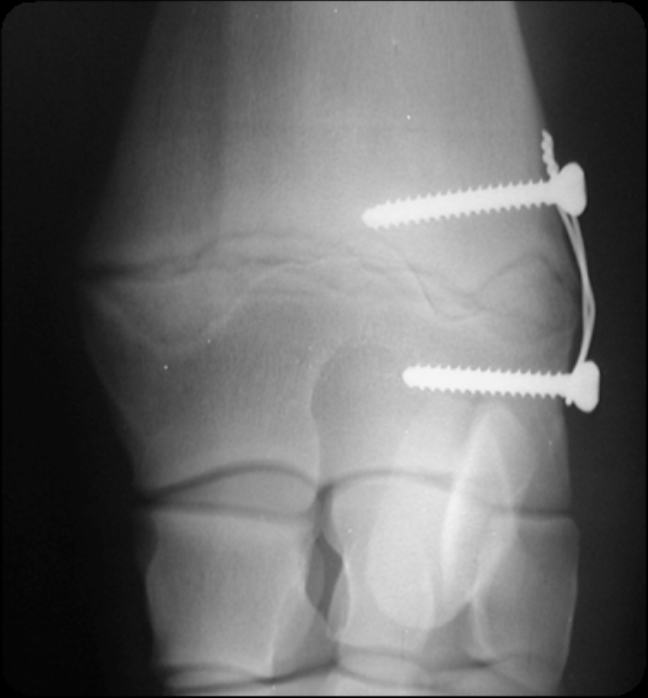

transphyseal bridging using screw and wire

commonly used in the carpus

two scres placed on either side of the physis, held with a figure 8 cerclage wire across physis